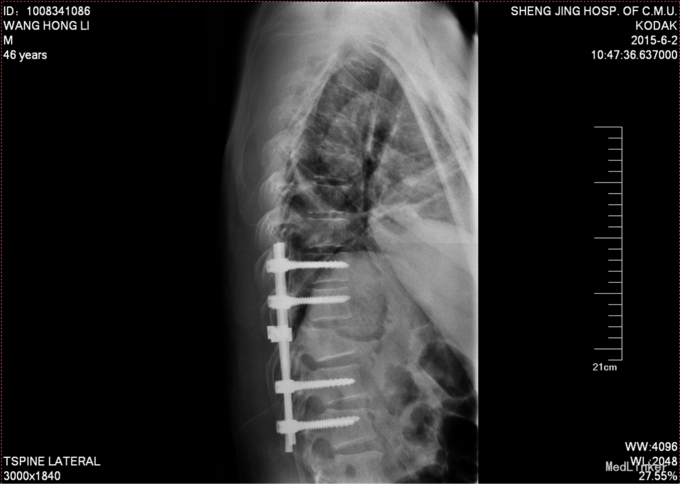

入院后完善检查,查无手术禁忌症后行胸11椎体骨折切开复位椎板减压椎弓根钉内固定术

患者术后肢具保护中下地行走,术后2年后行腰椎内固定物取出术,术后功能正常。